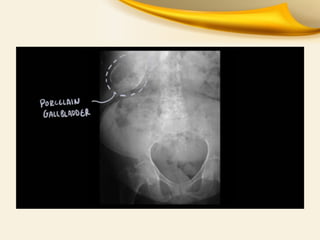

Chronic Cholecystitis

• Long-standing gallbladder inflammation almost

always due to gallstones.

• Chronically Inflammed Thickened Gallbladder

which is NONFunctioning NONdistending

• Extensive calcification due to fibrosis is called

porcelain gallbladder.

Chronic Cholecystitis • Long-standinggallbladder inflammation almost always due to gallstones. • Chronically Inflammed Thickened Gallbladder which is NONFunctioning NONdistending • Extensive calcification due to fibrosis is called porcelain gallbladder.